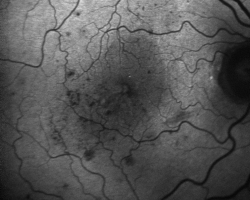

• Autofluorescence (2018)

hypoautofluorescence liée à l’œdème maculaire et aux hémorragies rétiniennes qui, par effet masque, empêchent la stimulation de l’epithélium pigmentaire rétinien